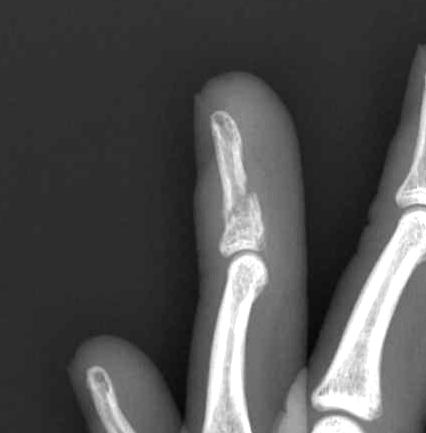

Mallet fractures

Mechanism

- axial load

- extensor tendon attached to bony fragment

Closed treatment

- mallet splint (Stack)

- expect 10o extensor lag with mild loss ROM

- good results with non – op management

ORIF

Indication

- volar subluxation of distal phalanx

- fragment > 50% joint surface

- chronic > 12 weeks old